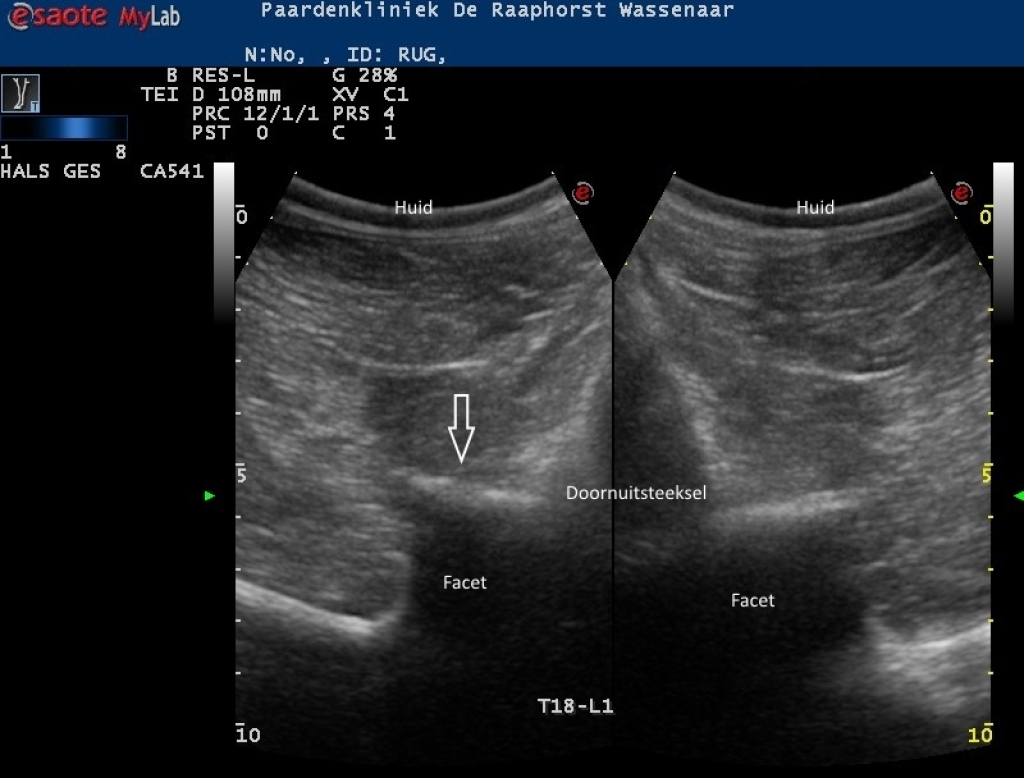

Links: Echobeeld van een licht artrotisch facetgewricht (links) op de thoracolumbale overgang

Rechts: Echobeeld van artrose van een facetgewricht in het lendengebied

Echobeeld van een licht artrotisch facetgewricht (links) op de thoracolumbale overgang

Echobeeld van artrose van een facetgewricht in het lendengebied